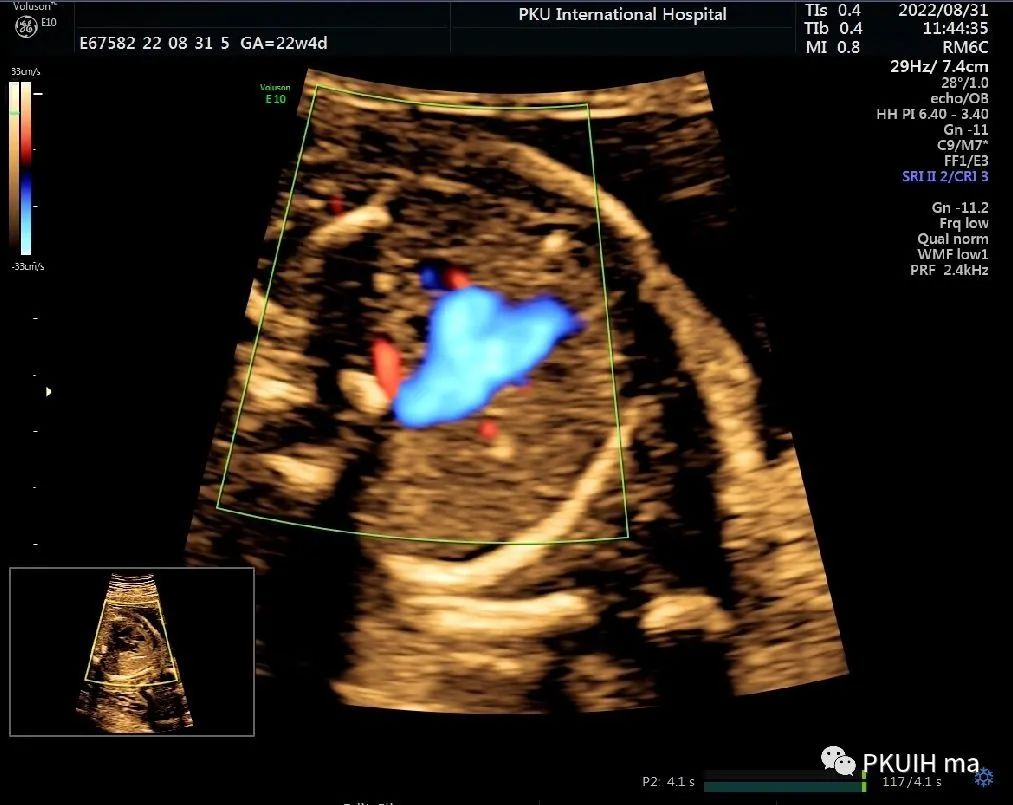

下面几张图都是右位主动脉弓、左动脉导管合并左锁骨下动脉迷走的病例,患儿出生后随访均无明显临床症状

主动脉弓走行于气管的右侧,与左位的动脉导管形成“U”型环(不完全血管环),包绕气管和食管。主动脉冠状切面可见左锁骨下动脉起自于主动脉弓降部,向左肩部走行。